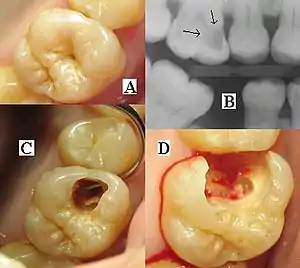

| Destruction of a tooth by dental caries and disease | |